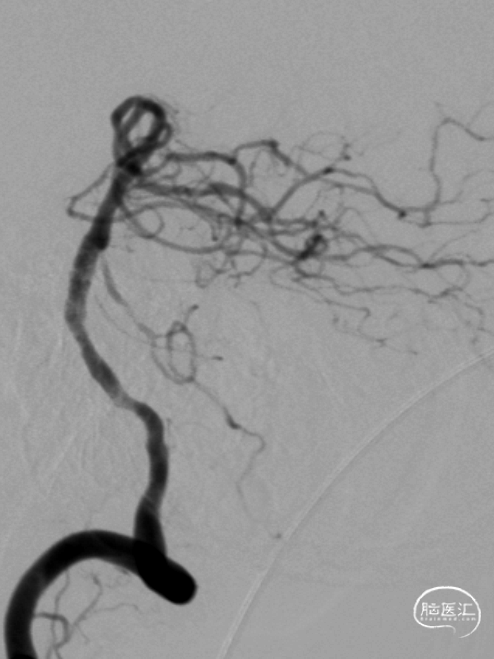

半年后复查造影:支架内无明显再狭窄。椎基底动脉通畅,前向血流mTICI3级。